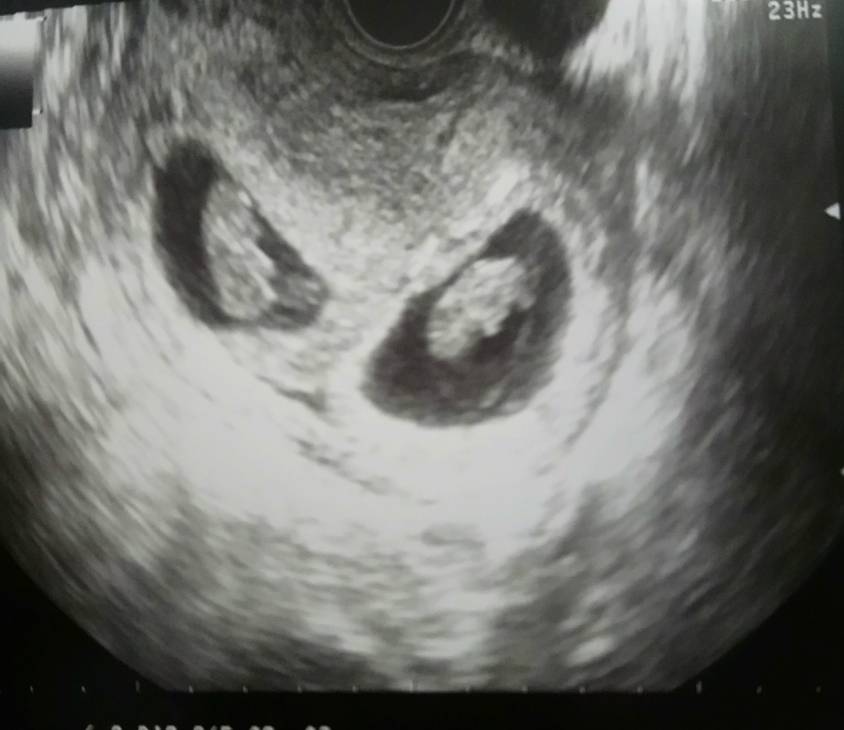

Tylko ja już tydz temu wylądowałam w szpitalu z krwawieniem, prawdopodobnie krwiak, do dziś plamię. Do tego jestem szczupła no i lekarze mi powiedzieli ze ciężko będzie donosić chociaż do 35 tygodnia